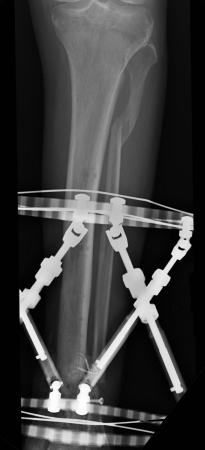

Postoperative (13th) images of left ankle

The image(s) displayed here were created following Liam's 13th surgery which was performed by Dr. Saunders. After a few hiccups getting

the surgery scheduled, Liam spent most of the September 13th afternoon in his 13th surgery. ;-) The surgery lasted about 5 hours and according

to the doctor, it was a good surgery. The 1st photo shows the new frame bracing that holds Liam's ankle together. The next series of photos show

various angles of the ankle and the rods that go from the frame into and through the left ankle. There was some concern that the swelling would

burst and allow for infection. Looks like we are now past that concern. Liam is still on antibiotics to ward of potential infection. The flesh

images show how the skin reacts to having the leg adjusted by the brace. The doctor has had to cut the skin to allow the rods to move freely.